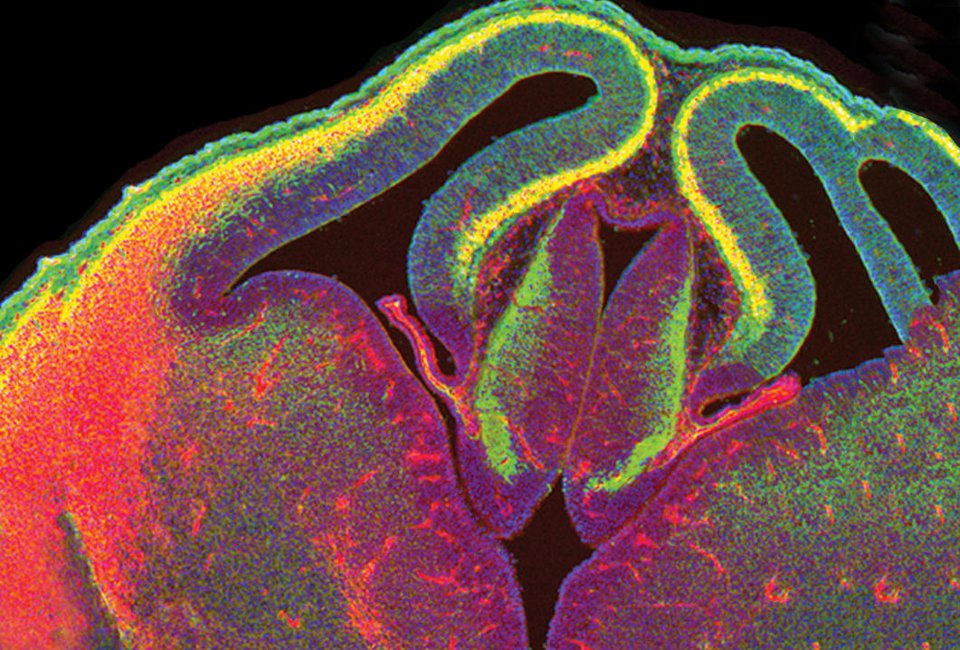

Η εξέλιξη του εγκεφάλου στα πρώτα εμβρυικά στάδια, είναι κάτι που προκαλεί μεγάλο ενδιαφέρον στους επιστήμονες. Ολα ξεκινούν από ένα κύτταρο, το οποίο συνεχώς διαιρείται. Κάθε «νεογέννητο» κύτταρο έχει την τάση να απομακρύνεται από το μητρικό του, ώστε να φτάσει στο επιθυμητό σημείο. Αυτή η διαδικασία περιγράφεται στην παραπάνω εικόνα.

Ο εγκέφαλος ενός ποντικιού 12 ημερών βρίσκεται ακόμα σε αρχικό στάδιο ανάπτυξης. Συνεχώς αναπτύσσεται, με συνεχόμενες διαιρέσεις. Τα καινούργια κύτταρα, που παράγονται από τα βλαστικά, περνούν στην εξωτερική μεριά ώστε να «ωριμάσουν». Για αυτό και το εξωτερικό χρώμα του φλοιού είναι πράσινο, ενώ ο πυρήνας του κατακόκκινος.